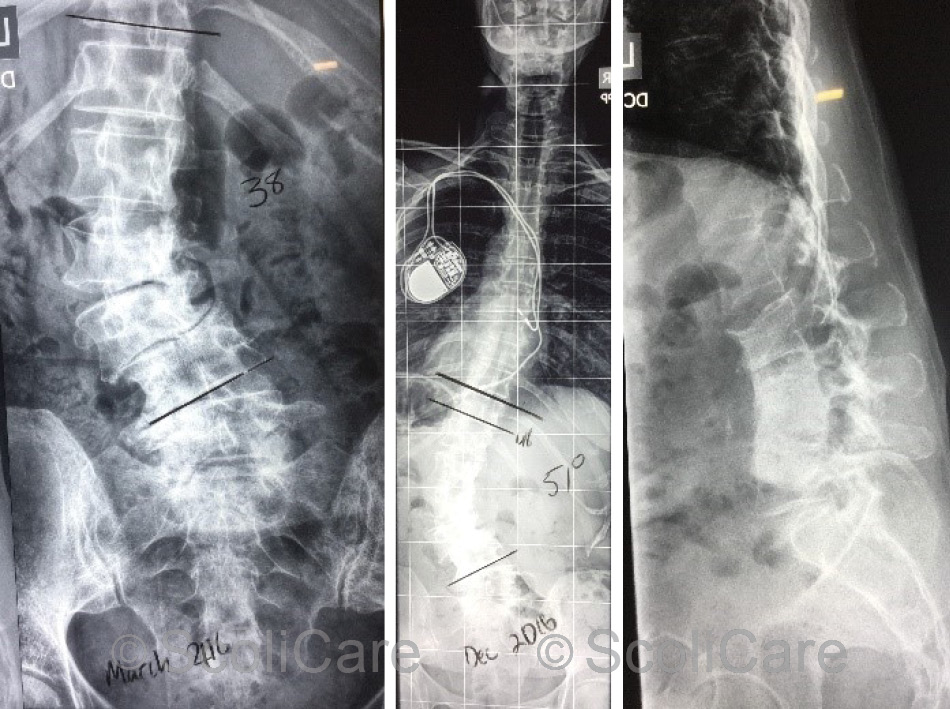

The patient had brought several forms of diagnostic imaging to the initial consultation. Plain films taken 10 months prior portrayed a 38° (Cobb) left lumbar scoliosis (Apex L2). Laterolisthesis was noted at L3/4 and significant spondylosis from L2-L5 (Figure 2).

The most recent films indicated that the patient’s scoliosis had progressed, now measuring 51° (Cobb). Computed tomography confirmed the findings from the x-ray and highlighted vacuum phenomena at L2/3 and L4/5 intervertebral disc levels.

Figure 2: Posteroanterior spine x-ray highlighting a 38° (Cobb) left lumbar scoliosis taken 10 months prior to the initial consultation (Left), Recent posteroanterior full spine x-ray highlighting a 51° (Cobb) left lumbar scoliosis (Middle), Recent lateral lumbar x-ray (Right).